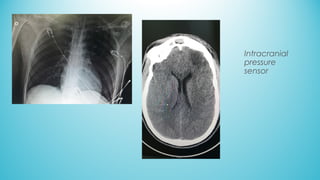

Intracranial

pressure

sensor

• DECEMBER 21TH: intracranial sensor, ICP=14